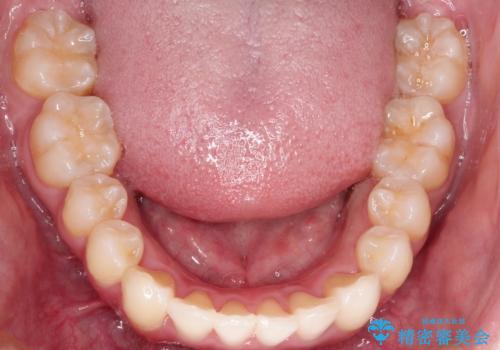

左上の前から2番目の歯が通常とは異なる形態をしており、左右対称にすることはできませんでしたが、インビザラインで周りに気づかれることなく矯正治療をおえることができ、満足していただけました。